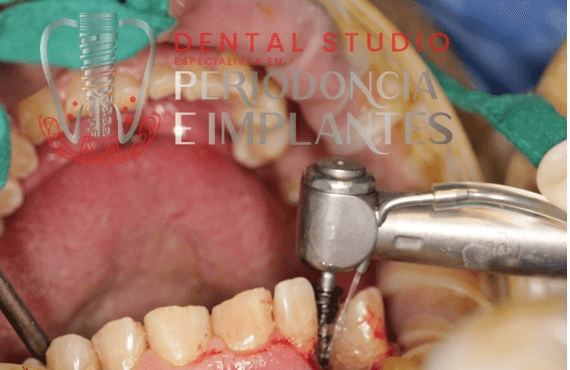

Implantes Dentales

Realizamos la colocación de implantes dentales con planificación computarizada, asegurando una integración óptima y duradera en tu boca, así como un seguimiento continuo para prevenir complicaciones.